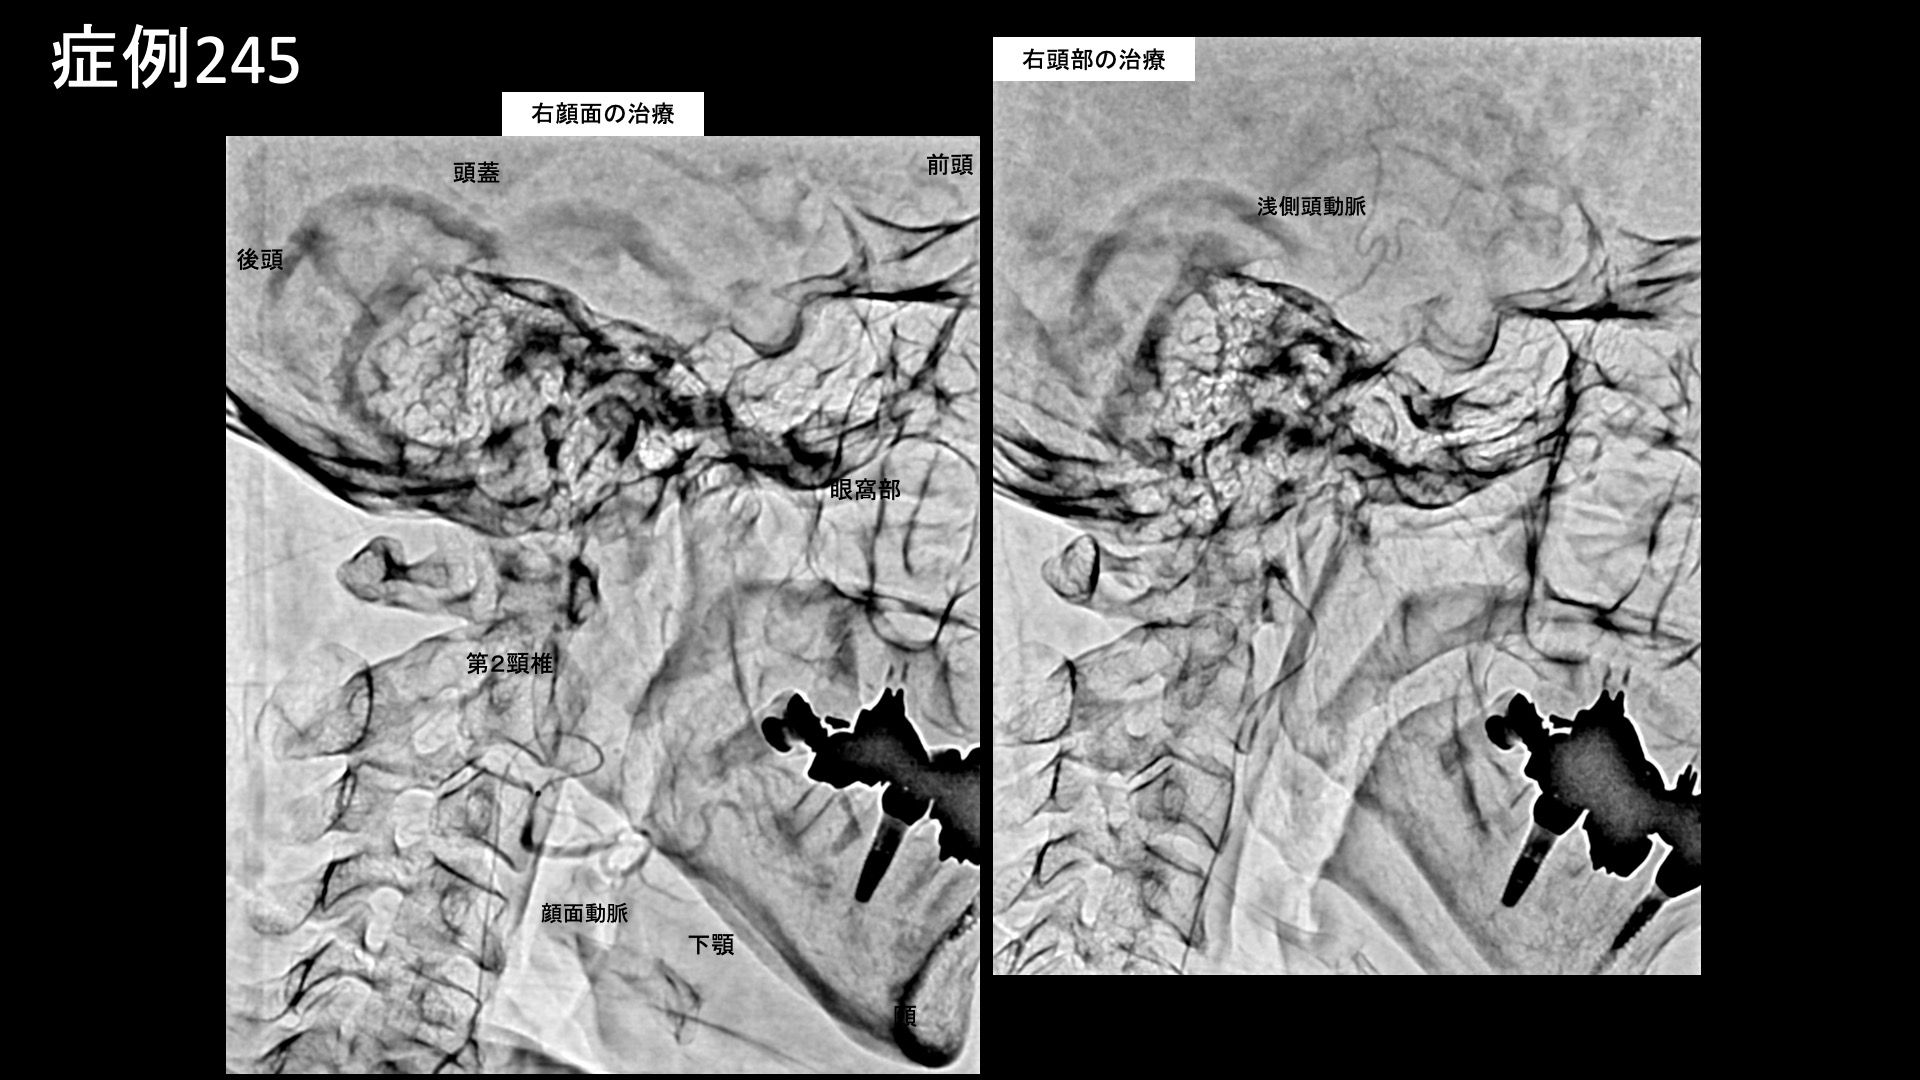

頸部の治療では、深頸動脈造影でモヤモヤ血管が濃染像として描出されました。首肩こり部位の治療を行った後、頭部・顔面では、浅側頭動脈、顎動脈、顔面動脈の各血管より治療を行いました。それぞれ再現痛を認めました。